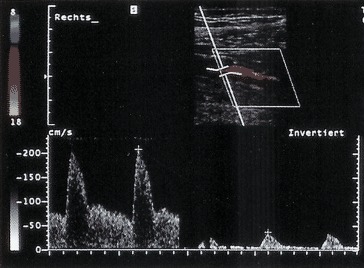

Intraaortale Ballongegenpulsation (◘ Abb. 1.3)

Platzierung des über die A. femoralis eingeführten Ballonkatheters in der Aorta descendens unterhalb des Subklaviaabganges. EKG-gesteuertes Aufblasen in der frühen Diastole steigert die Koronarperfusion. Deflation in der frühen Systole senkt die Nachlast und steigert das Schlagvolumen des Herzens. Indiziert im kardiogenen Schock (Kontraindikation bei Aorteninsuffizienz).